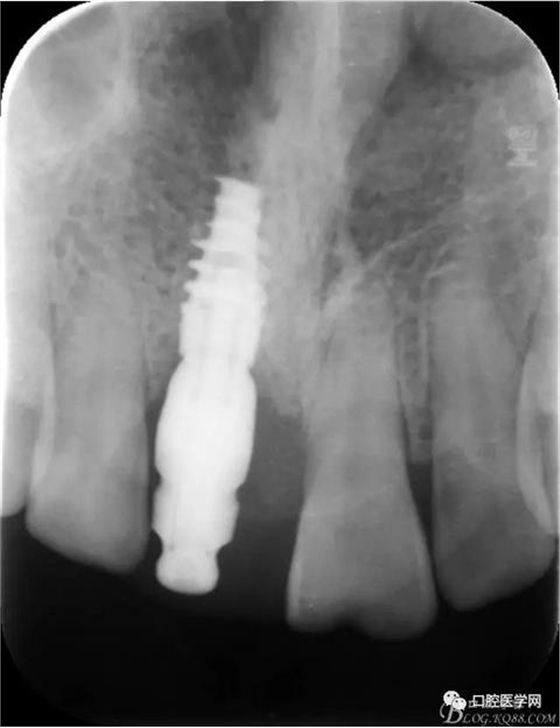

X 光 示:11 根折,根尖無明顯異常

診 斷:11 根折

圖1 術前X光片